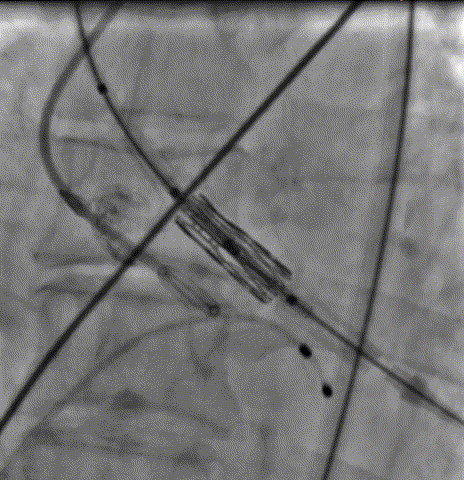

导丝顺利跨瓣

19mm球囊预扩排除冠脉风险

瓣膜输送跨瓣

瓣膜定位后